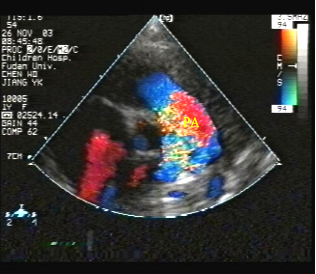

胸骨旁主动脉短轴观:

肺动脉内湍流频谱,

表明肺血流量增多,肺动脉瓣相对狭窄

(间接征象)

脉冲多普勒:

肺动脉瓣口流速增快,